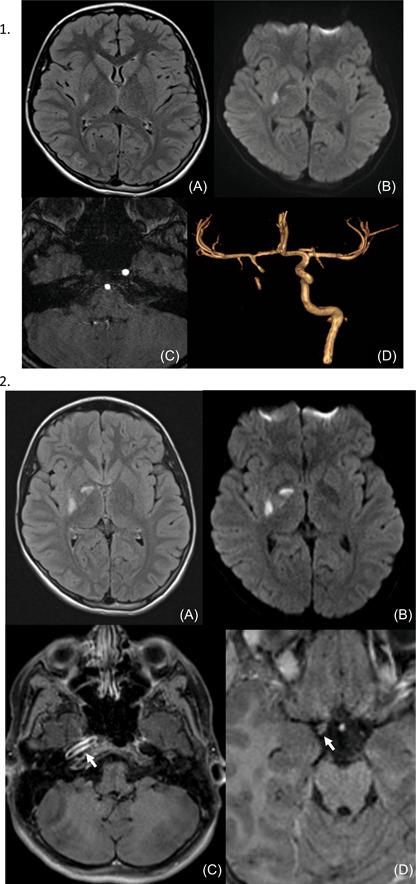

Cerebral CT and MRI showed an ischemic stroke of right sylvian artery. Magnetic resonance angiography performed upon resurgence of new symptoms was in favor of vasculitis on the right internal carotid and right sylvian artery. PCR SARS-CoV2 was positive for Omicron variant. She fully recovered after few days and was treated with acetylsalicylic acid and intravenous corticosteroids.

脑部CT和MRI显示右侧大脑中动脉缺血性中风。在新症状复发时进行的磁共振血管造影显示右侧颈内动脉和右侧大脑中动脉存在血管炎。新冠病毒PCR检测显示奥密克戎变种呈阳性。她在几天后完全康复,并接受了阿司匹林和静脉注射皮质类固醇治疗。